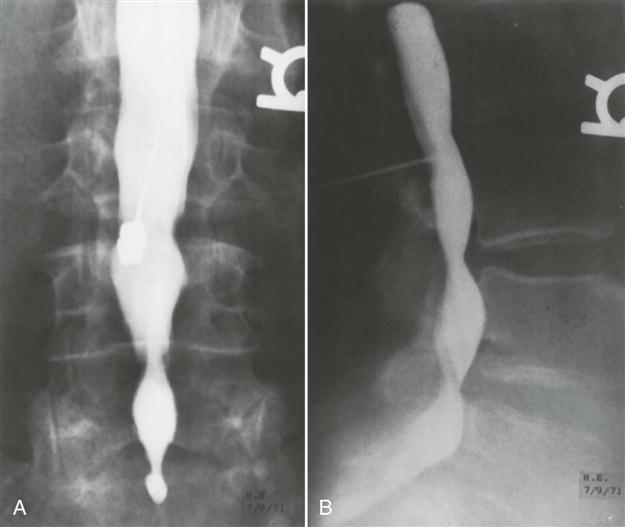

A myelogram, although seldom used today because of its complications and replacement by computed tomography (CT) scans and magnetic resonance imaging (MRI), can confirm the presence of a protruding intervertebral disc, osteophytes, a tumor, or spinal stenosis (Figures 9-113 through 9-115). The examiner must be careful of the side effects of myelograms, which include headache, stiffness, low back pain, cramps, and paresthesia in the lower limbs. Although side effects do occur, no permanent injuries have been noted.